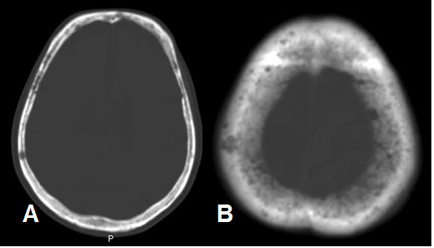

Fig 189. Mieloma.

A y B: TAC axial. Lesiones líticas en la bóveda craneana, por mieloma.